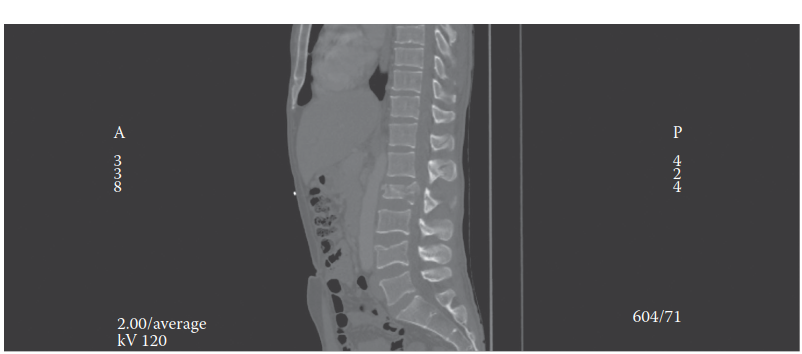

Standard anteroposterior and lateral radiographs provide an initial assessment of alignment and gross fracture morphology. However, thin-slice computed tomography with sagittal and coronal reconstructions is the gold standard for defining bony anatomy, facet subluxation, and the extent of canal compromise.

Magnetic Resonance Imaging is indispensable for evaluating the integrity of the Posterior Ligamentous Complex, intervertebral discs, and the spinal cord itself. Short Tau Inversion Recovery sequences are particularly sensitive for detecting ligamentous edema and epidural hematomas. MRI is strictly indicated in any patient with a neurological deficit, suspected tension-band injury not clearly visible on CT, or when the TLICS score is equivocal.